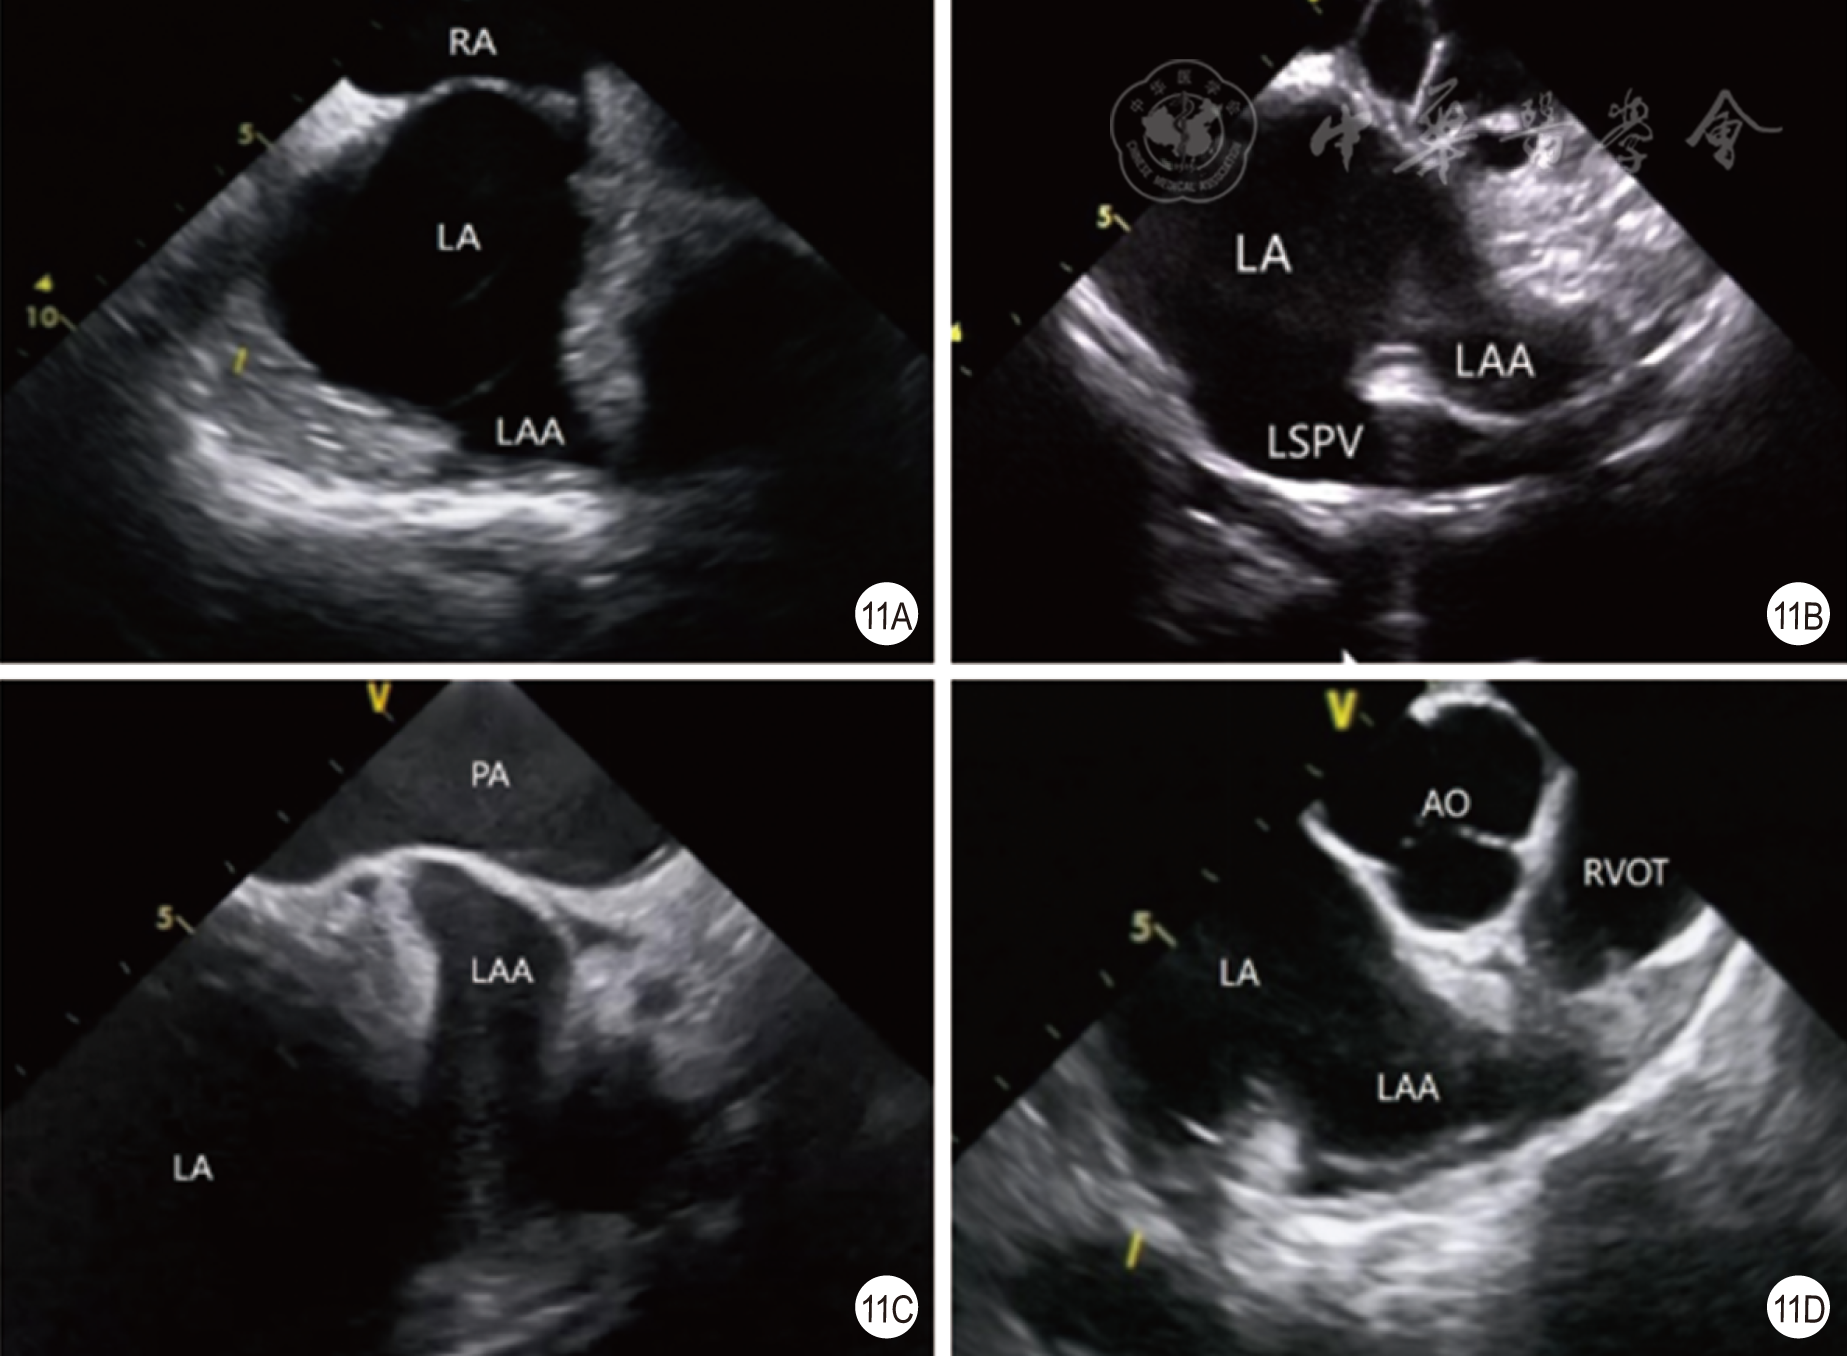

图11 利用心腔内超声心动图探查左心耳有无血栓(11A为左心房短轴观;11B为左心房长轴观;11C为肺动脉瓣上观;11D为右心室流出道观)RA为右心房,LA为左心房,LAA为左心耳,LSPV为左上肺静脉,PA为肺动脉,AO为主动脉,RVOT为右心室流出道